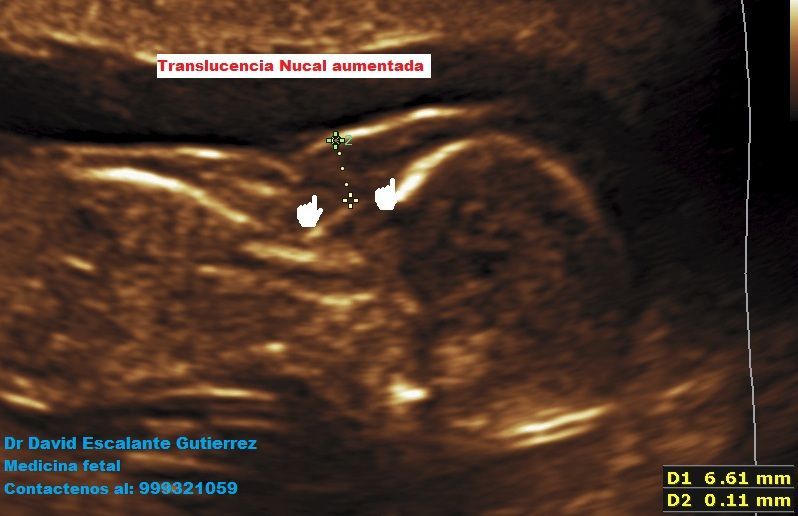

Realizamos las ecografías de viabilidad del embarazo, genética, morfológica, de bienestar fetal, ecocardiografías fetales, así como procedimientos invasivos como biopsia de vellosidades coriales y amniocentesis.